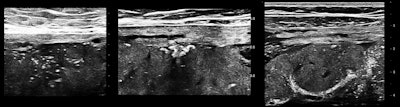

Placental architecture

Some or most of the placenta is accessible transabdominally for 15- to 20-MHz scanning in the third trimester with modern ultrasound units, especially when the placenta is anterior or anterolateral, or fundal. Viewed in this way, a normal placenta is far from homogeneous. Neglecting fluid spaces, vascular voids, infarcts, or other anechoic or hypoechoic patches, the improvement in contrast enables seeing punctate reflectors, representing corked-off vessels, and later in the course of this pathology, patches of increased reflectivity that imply, as elsewhere, sclerosis (see figures 1 and 2). Small-vessel disease of the placenta is of the greatest clinical importance.

So if you start seeing punctate reflectors in the placenta, you will think that a thrombophilia panel is a good idea, or, alternatively, if there is an abnormal maternal thrombophilia profile early in pregnancy, some sort of ultrasound surveillance for the emergence of small-vessel disease should be appropriate in the third trimester. The idea is to identify the risk and act to prevent placental sclerosis and its sequellae, growth retardation and/or hypoxic compromise of individual organs.